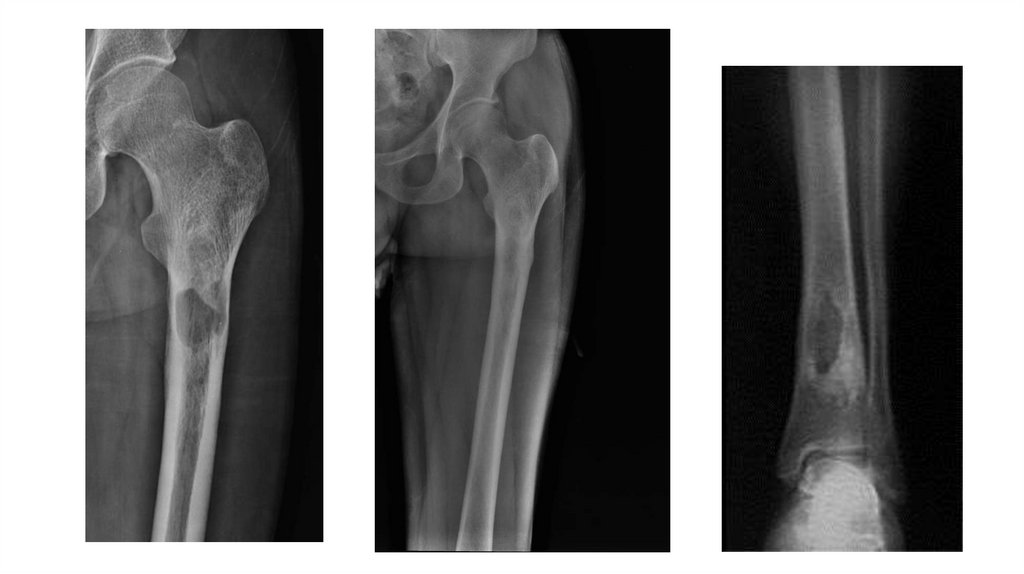

Воспалительные заболевания опорнодвигательного аппарата

«Воспалительные

заболевания опорнодвигательного аппарата»